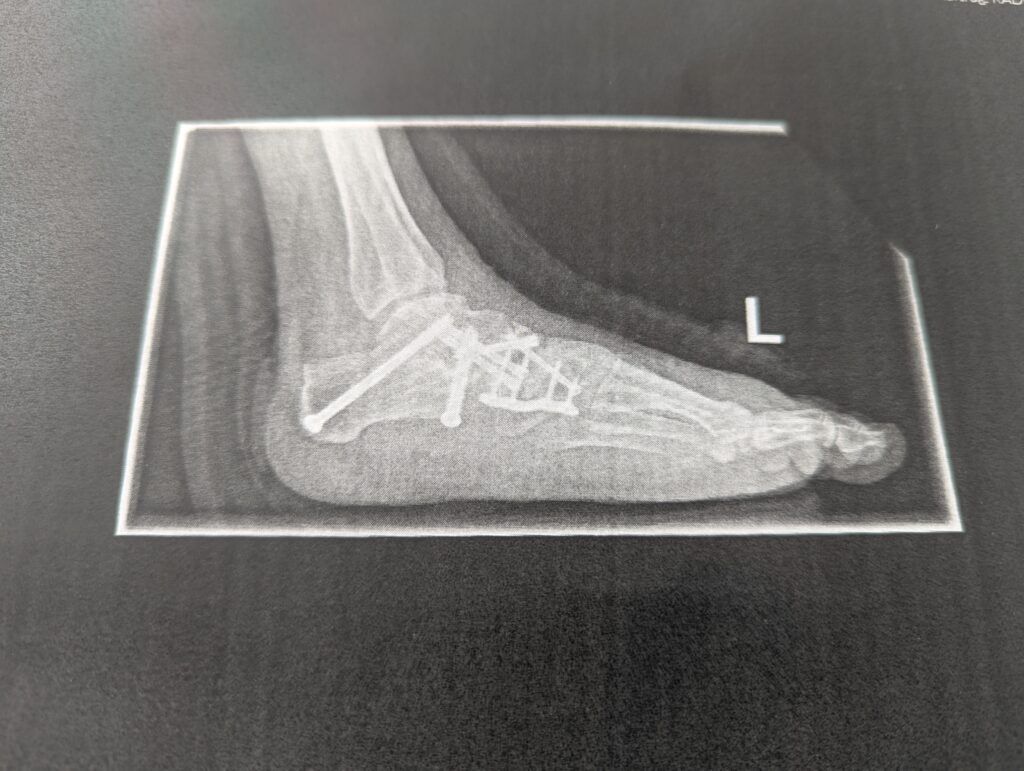

Danach wurde ich für meine Mühen mit einer kurzen Lymphdrainage belohnt, die von einer sehr lieben Ukrainerin durchgeführt wurde, der ich jeden Tag die verschiedensten Lerntipps für eine erfolgreiche Beschäftigung ihres Sechstklassohnes mit der französischen Sprache geben konnte, nachdem sie etwas verzweifelt an dem Klassenelternabend im Gymnasium von der Lehrerin erfahren hatte, dass fast die gesamte Klasse offensichtlich viel zu wenig fundierte Kenntnisse im Französischen besäße. Meine Ratschläge erfreuten nicht nur die Therapeutin, sondern lenkten mich wenigstens auch kurzfristig von meinen Schmerzen und dem Hadern mit der Gesamtsituation ab, in der ich mich tatsächlich nicht nur wie eine 80- oder 90-Jährige fühlte, sondern schockierenderweise auch mein Knochenzustand diesem wesentlich höherem Alter entsprach, wie es bei einer sofort veranlassten Knochendichtemessung grauenhafterweise diagnostiziert worden war. Als der Operateur mir am Tag nach der Operation von meinen so weichen Knochen berichtete, dachte ich ursprünglich noch, dass ihm dies doch beim Zersägen selbiger deutlich die Arbeit erleichtert hätte, die Beschaffenheit dieser gab jedoch großen Anlass zur Sorge, da unverzüglich eine Osteoporose – etwas, mit dem sich wohl die wenigsten Mittevierzigjährigen beschäftigen werden – erkannt wurde.

Bei der morgendlichen Visite am Entlassungstag begutachtete der Operateur meinen Fuß und war mit dem Ergebnis so weit zufrieden. „Wir haben so viele Knochen zersägt, da sind die großen Blutergüsse völlig normal.“ beruhigte er mich. Nachdem ich noch genauestens instruiert wurde, wie lange kein Wasser an meinen Fuß darf – ich leide jetzt schon sehr darunter, in diesem Herbst und Winter in keiner Weise meinem liebgewonnenen Ritual des wöchentlichen Eisbadens nachgehen zu können – ermahnte er mich beim Rausgehen noch einmal eindringlich, was es als allerwichtigstes für die kommenden sechs bis acht Wochen zu beachten gäbe. Verletzt, wie sich einige meiner Familie mir gegenüber auch während meiner Krankenhauszeit verhalten haben und wahrscheinlich auch der Übermüdung geschuldet, verstand ich dabei zunächst etwas ganz anderes, als wie es der Professor tatsächlich gesagt hatte. „Nicht aufregen!“, er hatte jedoch „Auf keinen Fall auftreten!“ gesagt…Immerhin fällt mir das Auftretverbot noch etwas leichter als der Vorsatz der Gelassenheit…